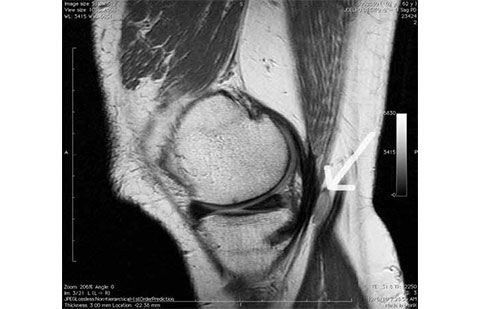

Exame de ressonância do joelho em que se observa um cisto na região posterior (seta)